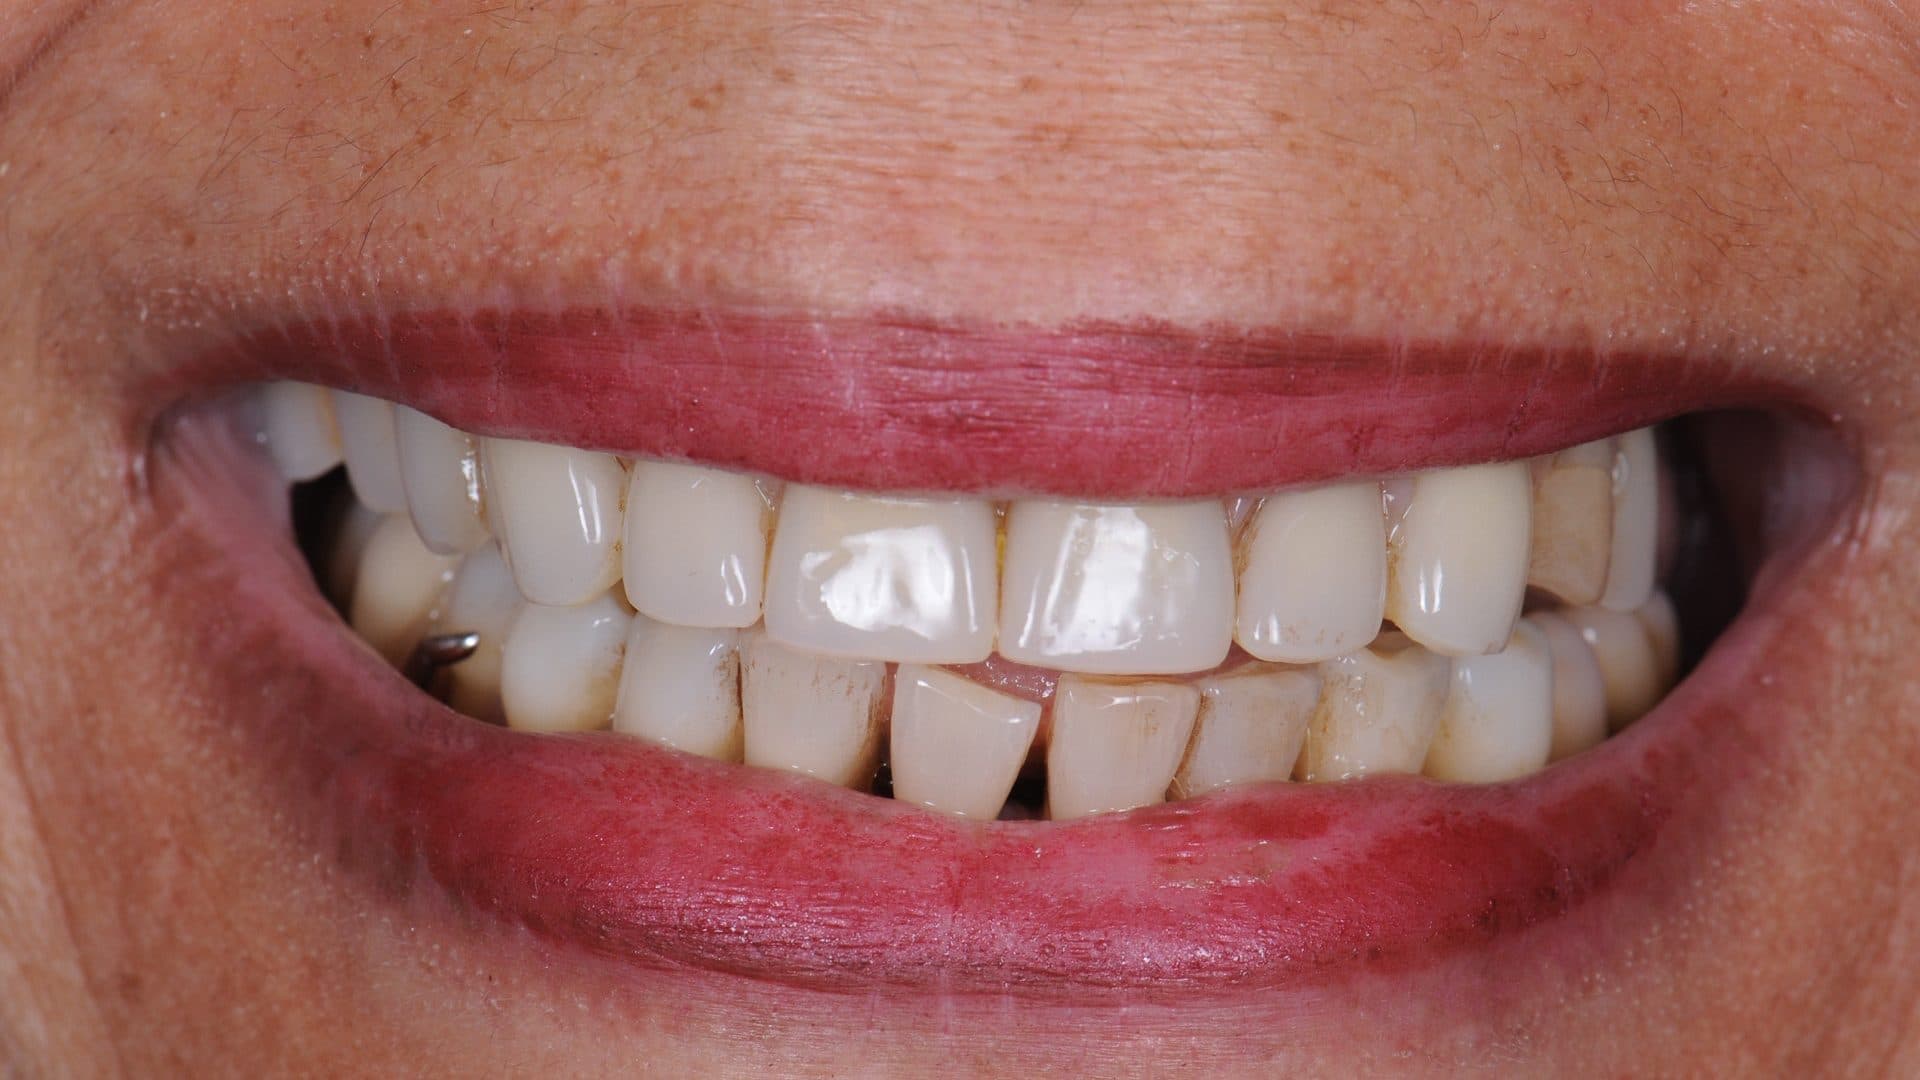

ii. The access holes for the screws are located near the edges of the front teeth and in the middle of the back teeth. Any deviation from this will severly affect level of comfort, speech, and also cleanability (See pictures);

Ideal Situation

Examples Of Poor Standards